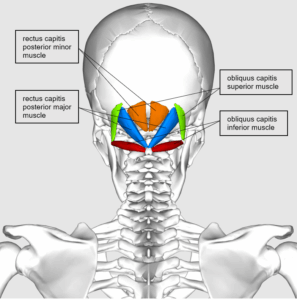

頭蓋内圧や脳圧の亢進、または頭蓋内高血圧の症状をお持ちの方が頻繁に来院されています。目の奥から頭痛が発生したり、心臓の鼓動に合わせて聞こえる拍動性耳鳴りがあったり、悪心、嘔吐、めまいを訴えられます。一晩中横になっている姿勢では脳浮腫がさらに悪化する可能性があるため、朝起きる時に頭痛があり、咳をする時や頭を下げる時のように頭蓋内圧を増加させる行為によって頭痛がさらに悪化するともおっしゃいます。また、首、肩、背中部位の痛みが多く、視神経浮腫による羞明や目のかすみといった眼症状を伴い、耳鳴り、ジストニア、斜頸、後頸部痛などの症状を訴えられます。